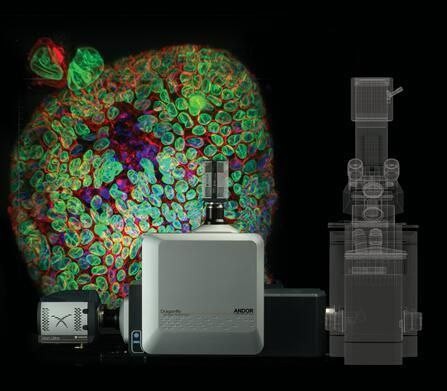

Dragonfly多点扫描共聚焦成像系统

项目类型

器械质押区

起投金额

18000USDT

每日释放:0.75

释放周期:70 天

已购: 2000

剩余: 0